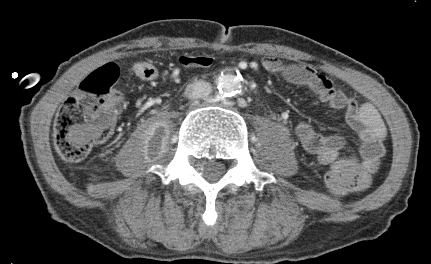

黄色ブドウ球菌による化膿性脊椎炎に合併した腸腰筋膿瘍のCT

右腸腰筋内に造影効果を伴う病変と内部が低吸収域の病変を認める。